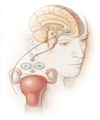

Amenorreia

Compartimento IV?

Hipotálamo.

GO: Amenorreia, SUA e infertilidade

Amenorreia

Compartimento III?

Hipófise.

GO: Amenorreia, SUA e infertilidade

Amenorreia

Compartimento II?

Ovário.

GO: Amenorreia, SUA e infertilidade

Amenorreias

Compartimento I?

Útero e vagina.